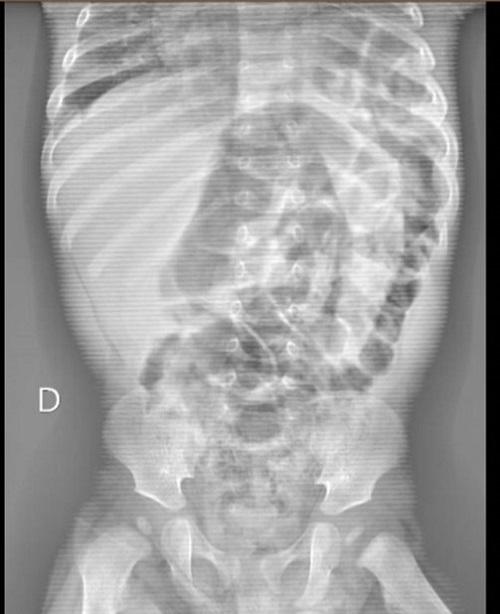

Se completa el estudio con una analítica, sin alteraciones, y una radiografía de tórax (Fig. 2) informada como consolidación basal izquierda sin poder descartar derrame pleural, motivo por el cual se decide realizar ecografía torácica donde se observa una imagen compatible con una hernia diafragmática congénita izquierda (Fig. 3).

| Figura 2. Hernia diafragmática congénita de presentación tardía (paciente de 6 meses): radiografía de tórax con imagen de consolidación basal izquierda; dudosa imagen aérea subdiafragmática |

La sospecha clínica y la realización de una radiografía de tórax son la clave para el correcto diagnóstico. Sin embargo, en un 25% de los casos su interpretación puede ser errónea, precisándose otras pruebas3. Debemos tener en cuenta que una radiografía torácica normal no excluye el diagnóstico, ya que la HDC puede simular diferentes entidades como neumonía lobar, tumores, malformación quística adenomatoidea congénita pulmonar, neumotórax o derrame pleural6.

Nuestro paciente presentó un cuadro de llanto persistente en posible relación con dolor abdominal, llegándose al diagnóstico tras la realización de una radiografía de tórax con una imagen sospechosa que se confirmó en la ecografía torácica. Dada su estabilidad clínica y a que luego permaneció asintomático, se prefirió completar el estudio diagnóstico previo a la realización de la cirugía. Nuestro caso, refleja la amplia variedad de manifestaciones clínicas de la HDC y la dificultad en su diagnóstico en los casos asintomáticos o poco sintomáticos.